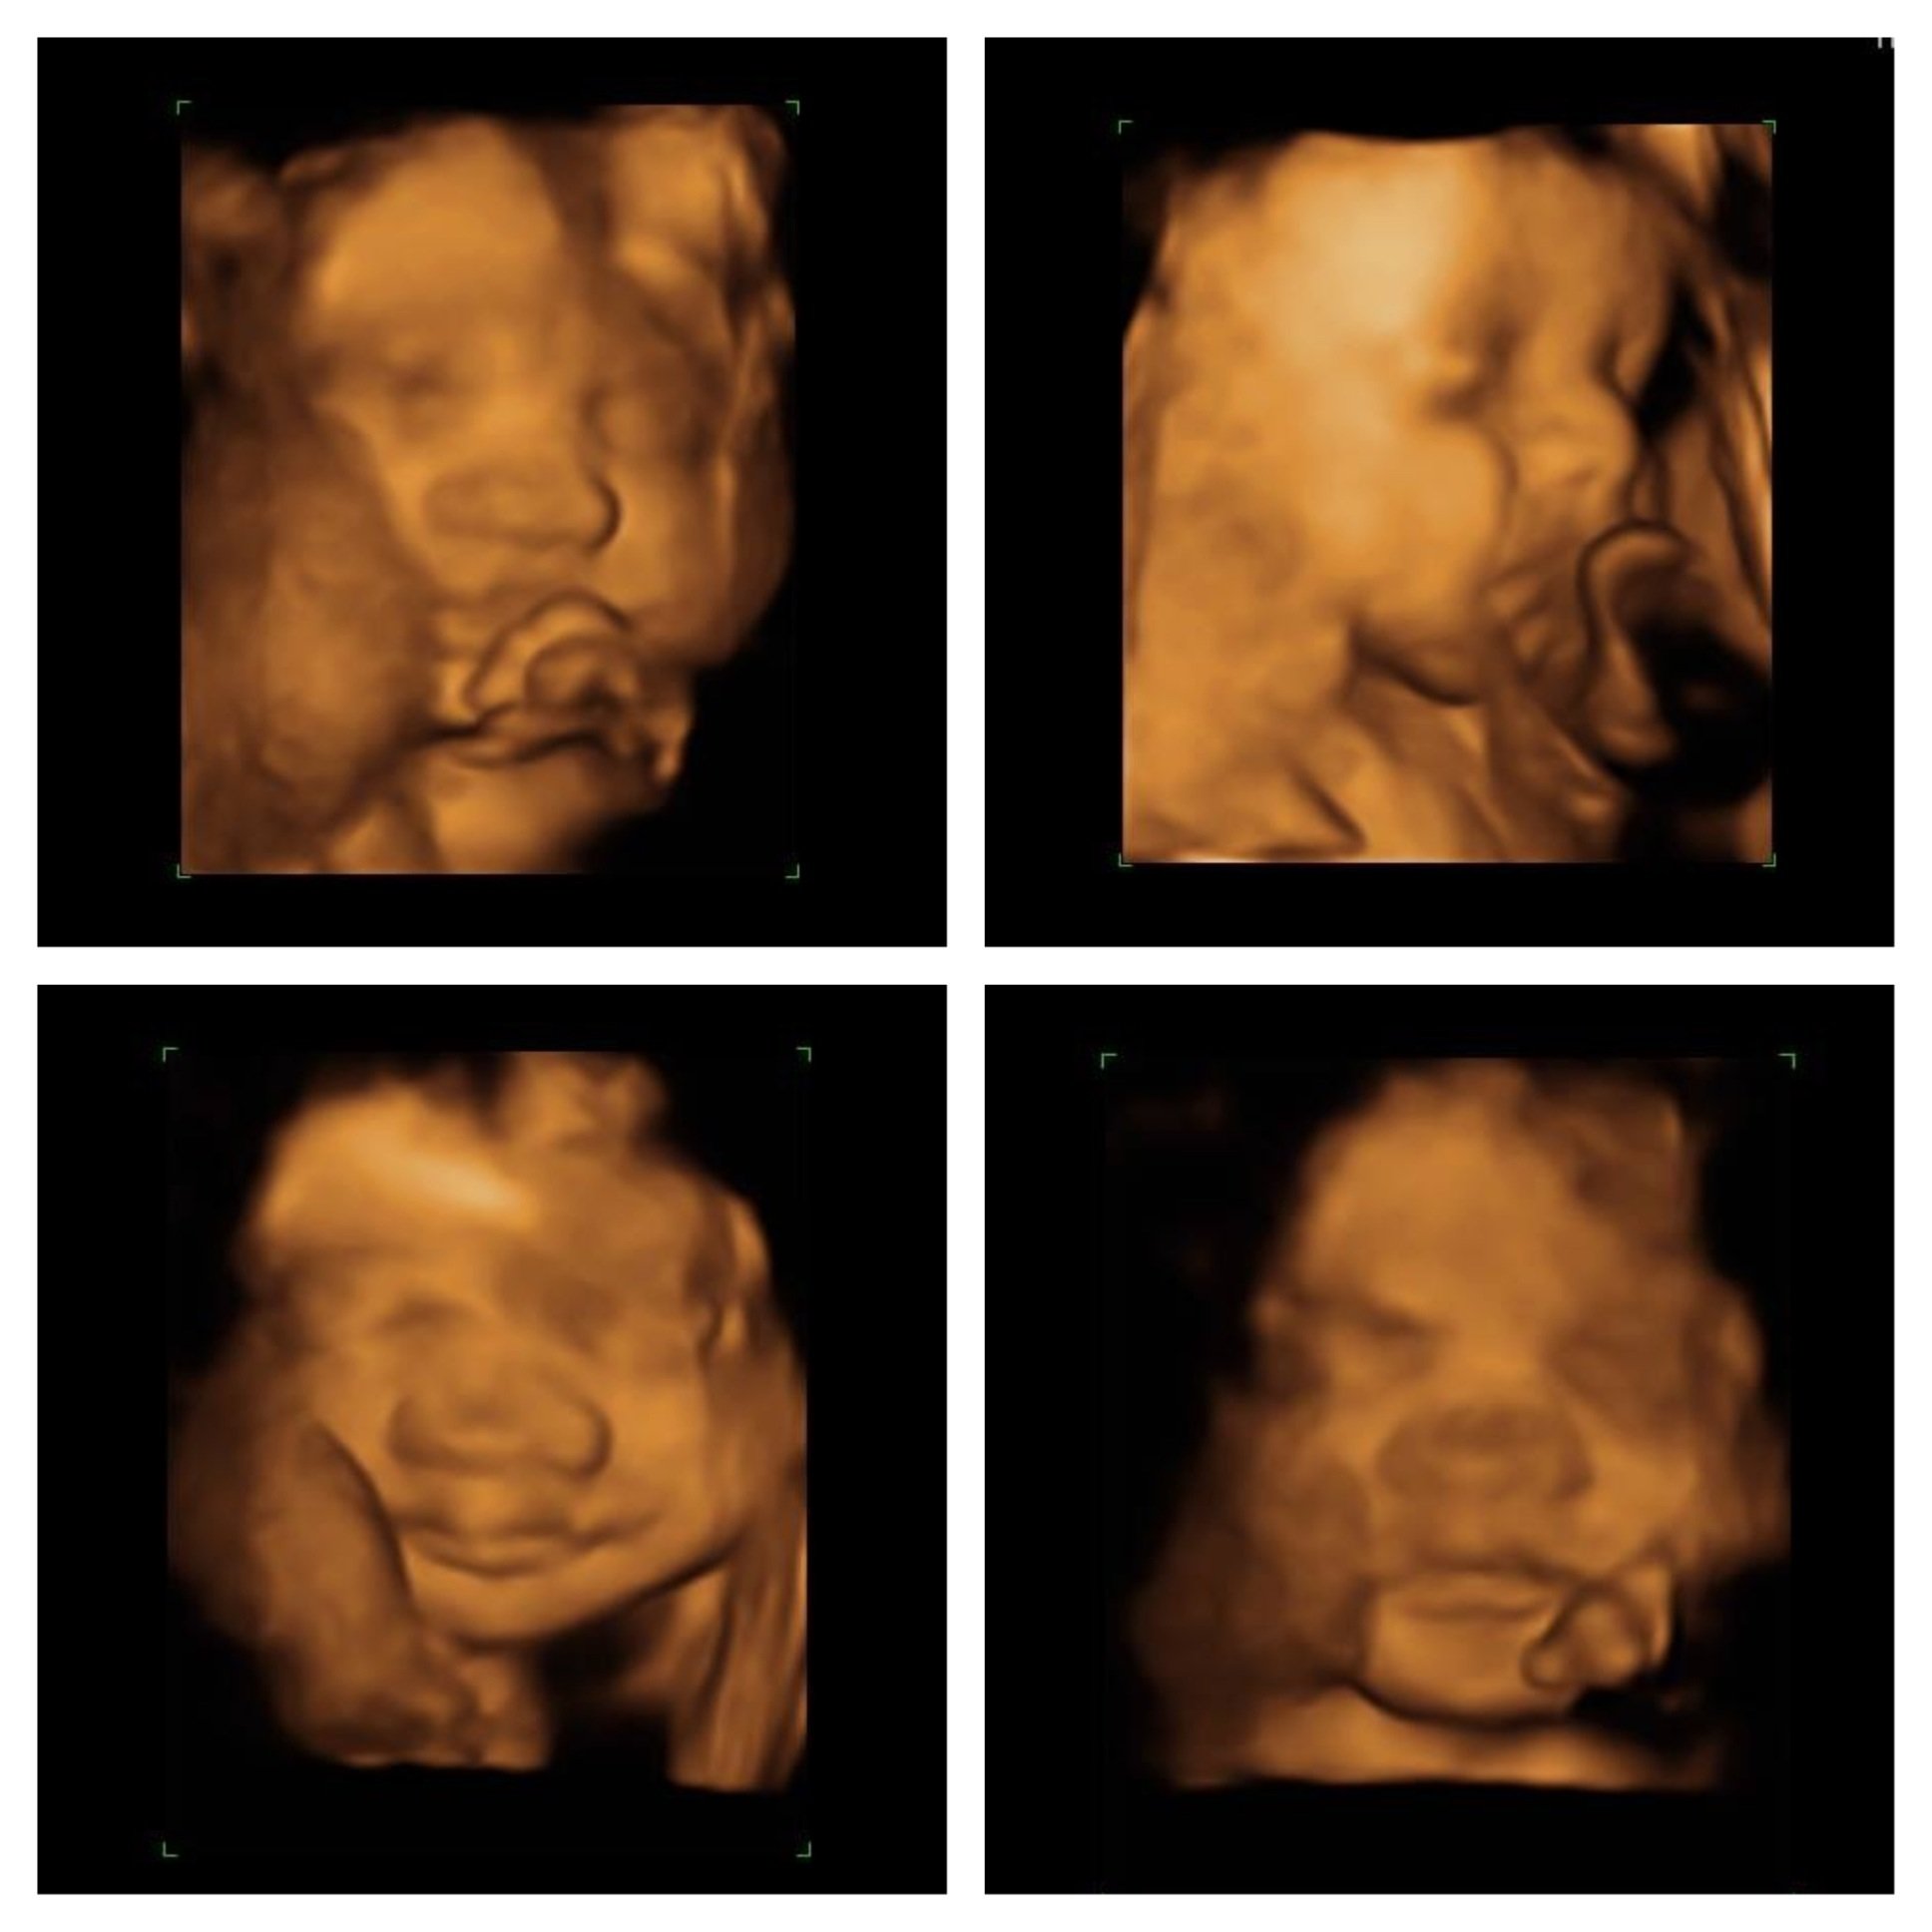

Patiently waiting for little brother!